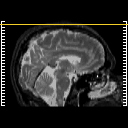

MR Study #6, March 17, 1991 -- Slice #51

[Home][Help][Clinical][Tour 1][Tour 2] Slice 51

Click on sagittal image to select slice. Click on thin tickmark to change timepoint, or thick tickmark for overlay.